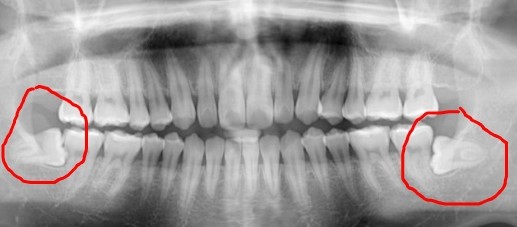

빨간색 원 안 누워있는 사랑니가 보이시죠?

보통 많은 경우에서 사랑니가 옆으로 누워서

나거나 잇몸에 살짝 덮여있어 일부만 보이는

경우, 치아와 잇몸 사이에 세균이 서식해

염증을 일으킬 가능성이 많아 뽑는 것이 좋습니다.